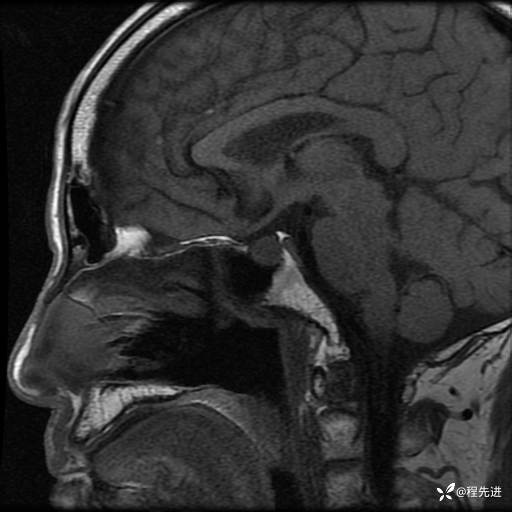

MRI平扫+增强:

T1: